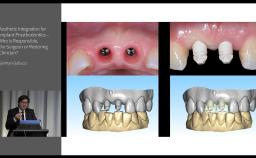

German Gallucci

Boston, United States